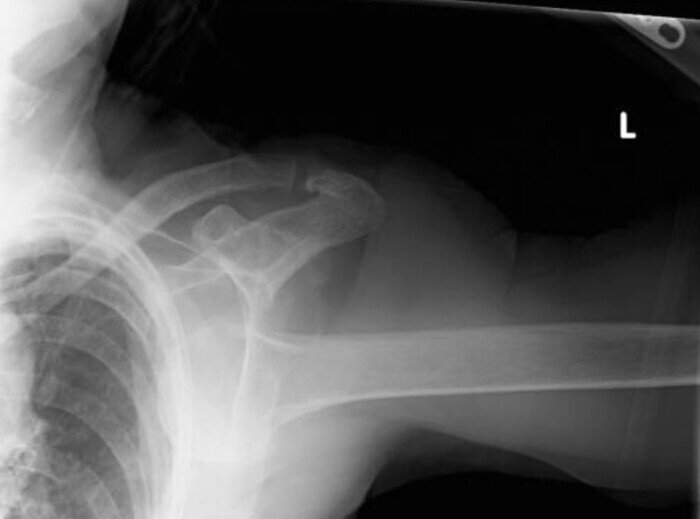

Пациентка, 90 лет, упала в доме престарелых. Доставлена по скорой. Плечо в суставе неподвижно, плечо находится в зафиксированной абдукции (зафисированное положение отведения). Из-за выраженного болевого синдрома был сделан 1 ренгеновский снимок:

Где несложно заметить полный вывих плечевого сустава.

Интересен, правда, то, куда вывихнуто плечо: вниз, т.е. головка плечевой кости (красным) находится вне суставной впадины (оранжевым) под коракоидным отростком лопатки (синим):

Что говорит о самом редком из 3-х возможных вывихов плечевого сустава, а именно нижнем вывихе или по-латински "luxatio erecta", который встречается лишь в 0.5% случаев (98% классический передний вывих, примерно 1.5% - задний вывих).

Лечится закрытой репозицией под наркозом, и дальше консервативно. Оперативное лечение (реконструкция ротаторной манжеты или повреждений суставной губы) показано, в основном, молодым активным пациентам после предварительной МРТ-диагностики.